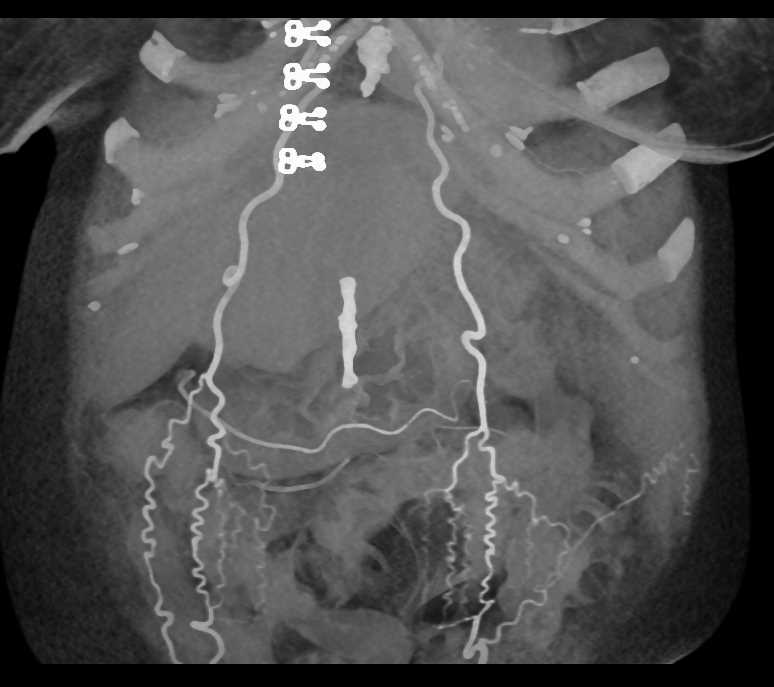

Collateral Vessels in the Abdominal Wall due to Liver Disease